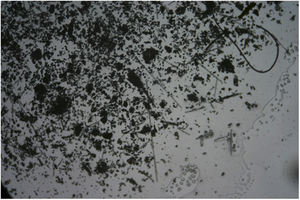

Pruebas complementariasLa analítica de sangre, que incluía IgE, no mostró alteraciones significativas. Se realizaron pruebas epicutáneas con la batería estándar del Grupo Español de Investigación en Dermatitis de Contacto y Alergia Cutánea, con un resultado negativo. La biopsia mostró la presencia de una ampolla hemorrágica subepidérmica e hiperqueratosis con acantosis, todos ellos cambios compatibles con una lesión por rascado (fig. 2). En la muestra obtenida mediante la tira adhesiva se apreciaron numerosos fragmentos lineales de diámetro variable en microscopía de luz polarizada, compatibles con fibra de vidrio (fig. 3).

ComentarioLa fibra de vidrio es un material manufacturado ampliamente utilizado en el ámbito de la construcción, aunque debido a sus propiedades de aislamiento térmico, acústico y eléctrico, su uso no se limita de forma exclusiva a este sector. Se trata de un material químicamente inerte que no desarrolla sensibilización, si bien las resinas y otros aditivos utilizados en los productos finales que contienen fibra de vidrio podrían eventualmente generarla, y por ende inducir cuadros de eccema alérgico de contacto1. No obstante, la DFV pura, descrita por primera vez por Sulzberger y Baer en 19422, es una dermatitis de contacto irritativa considerada una causa frecuente de dermatitis ocupacional, cuyo mecanismo fisiopatogénico consiste en la penetración de fragmentos de vidrio a través de la capa córnea, produciendo una irritación mecánica3. Aunque menos descrito, es también posible el mecanismo aerotransportado4. Desde un punto de vista de clínico, se objetivan con frecuencia excoriaciones secundarias a un prurito incoercible, que en última instancia pueden simular cuadros de prurigo, dentro de un amplio espectro de lesiones eccematosas. Cabe destacar que la intensidad de la irritación es proporcional al diámetro de los fragmentos, e inversamente proporcional a su longitud. La anamnesis resulta fundamental para la identificación de una exposición a la fibra de vidrio, por lo que resulta primordial conocer la existencia de esta entidad. Un obstáculo a su reconocimiento consiste en que exposiciones prolongadas generan tolerancia a la fibra, mientras que son los pacientes con exposiciones cortas los que desarrollan lesiones5. Las pruebas de contacto no son útiles en su diagnóstico por lo expresado con anterioridad, aunque pueden tener relevancia para identificar sensibilizaciones concomitantes a los aditivos. El estudio histopatológico, aunque de baja rentabilidad como ilustra nuestro caso, podría eventualmente poner de manifiesto fragmentos de vidrio birrefringentes engarzados en la capa córnea3. Una prueba sencilla y no cruenta es la obtención de muestra cutánea de la zona de lesión mediante tira adhesiva, con la consiguiente visualización de fragmentos de fibra de vidrio entre restos córneos mediante microscopía electrónica6, lo cual permite llegar a un diagnóstico de certeza.